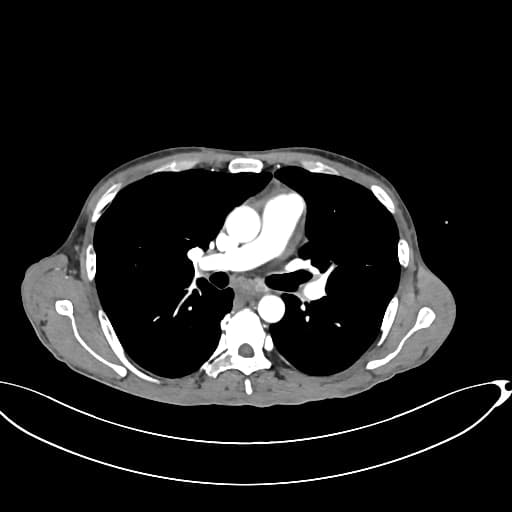

Axial C+ portal venous phase

- Khối dạng thùy, không đồng nhất (lobulated heterogeneous mass) ở đuôi tụy, phát triển vào và gây tắc đại tràng tại khúc nối lách (splenic flexure).

- Khối cũng xâm lấn tĩnh mạch thận trái và bể thận trên cực thận trái, dẫn đến hình ảnh thận trái chậm (delayed left nephrogram).

- Tĩnh mạch lách bị tắc kèm theo giãn tĩnh mạch vị ngắn (short gastric varices).

- Nhiều tổn thương di căn lan tỏa ở thuỳ gan trái.

- Có thể có cục huyết khối nhỏ gây thuyên tắc động mạch phân thùy ở phân thuỳ dưới thùy dưới phải (subsegmental right lower lobe artery) – hình ảnh đầu tiên.

- Các nốt nhỏ ở các thuỳ dưới được ghi nhận trên hình ảnh, gợi ý tổn thương di căn.

Trường hợp này là biểu hiện muộn của ung thư biểu mô tuyến tụy (pancreatic adenocarcinoma), với vị trí khối u nằm ở đuôi tụy. Khi khối u nguyên phát nằm ở đầu tụy, bệnh nhân thường có biểu hiện sớm như vàng da hoặc viêm tụy. Tuy nhiên, trong trường hợp này, bệnh nhân lại đến khám do tắc đại tràng. Ngoài ra, còn có tình trạng tắc tĩnh mạch lách kèm giãn tĩnh mạch vị ngắn, tắc tĩnh mạch thận trái và bể thận trên cực thận trái dẫn đến hình ảnh thận trái chậm, cùng với các tổn thương di căn rộng ở thuỳ gan trái.